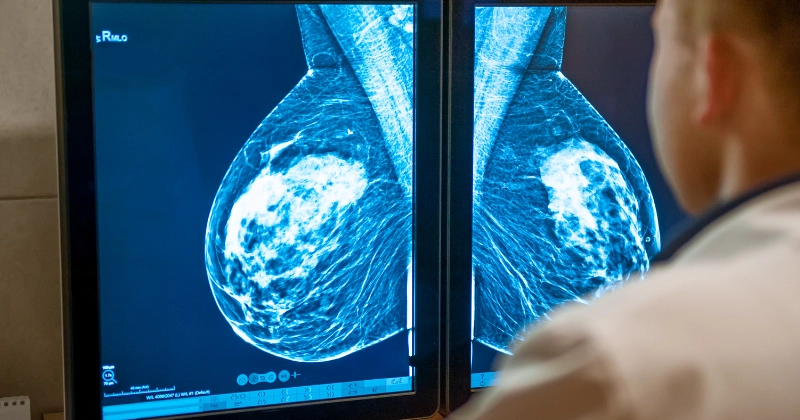

우리나라 여성에게 가장 많이 발생하는 암 1위는 '유방암'입니다.

유방암은 조기 발견 시 치료율과 완치율이 매우 높은 병으로 조기 발견과 진단을 받는 것이 매우 중요합니다.

우리나라는 국가 암 검진을 통해 40대 이후에는 2년에 한 번씩 무료로 유방 촬영술을 진행할 수 있기 때문에 정기적인 진단 검사를 받아보는 것도 추천드립니다.